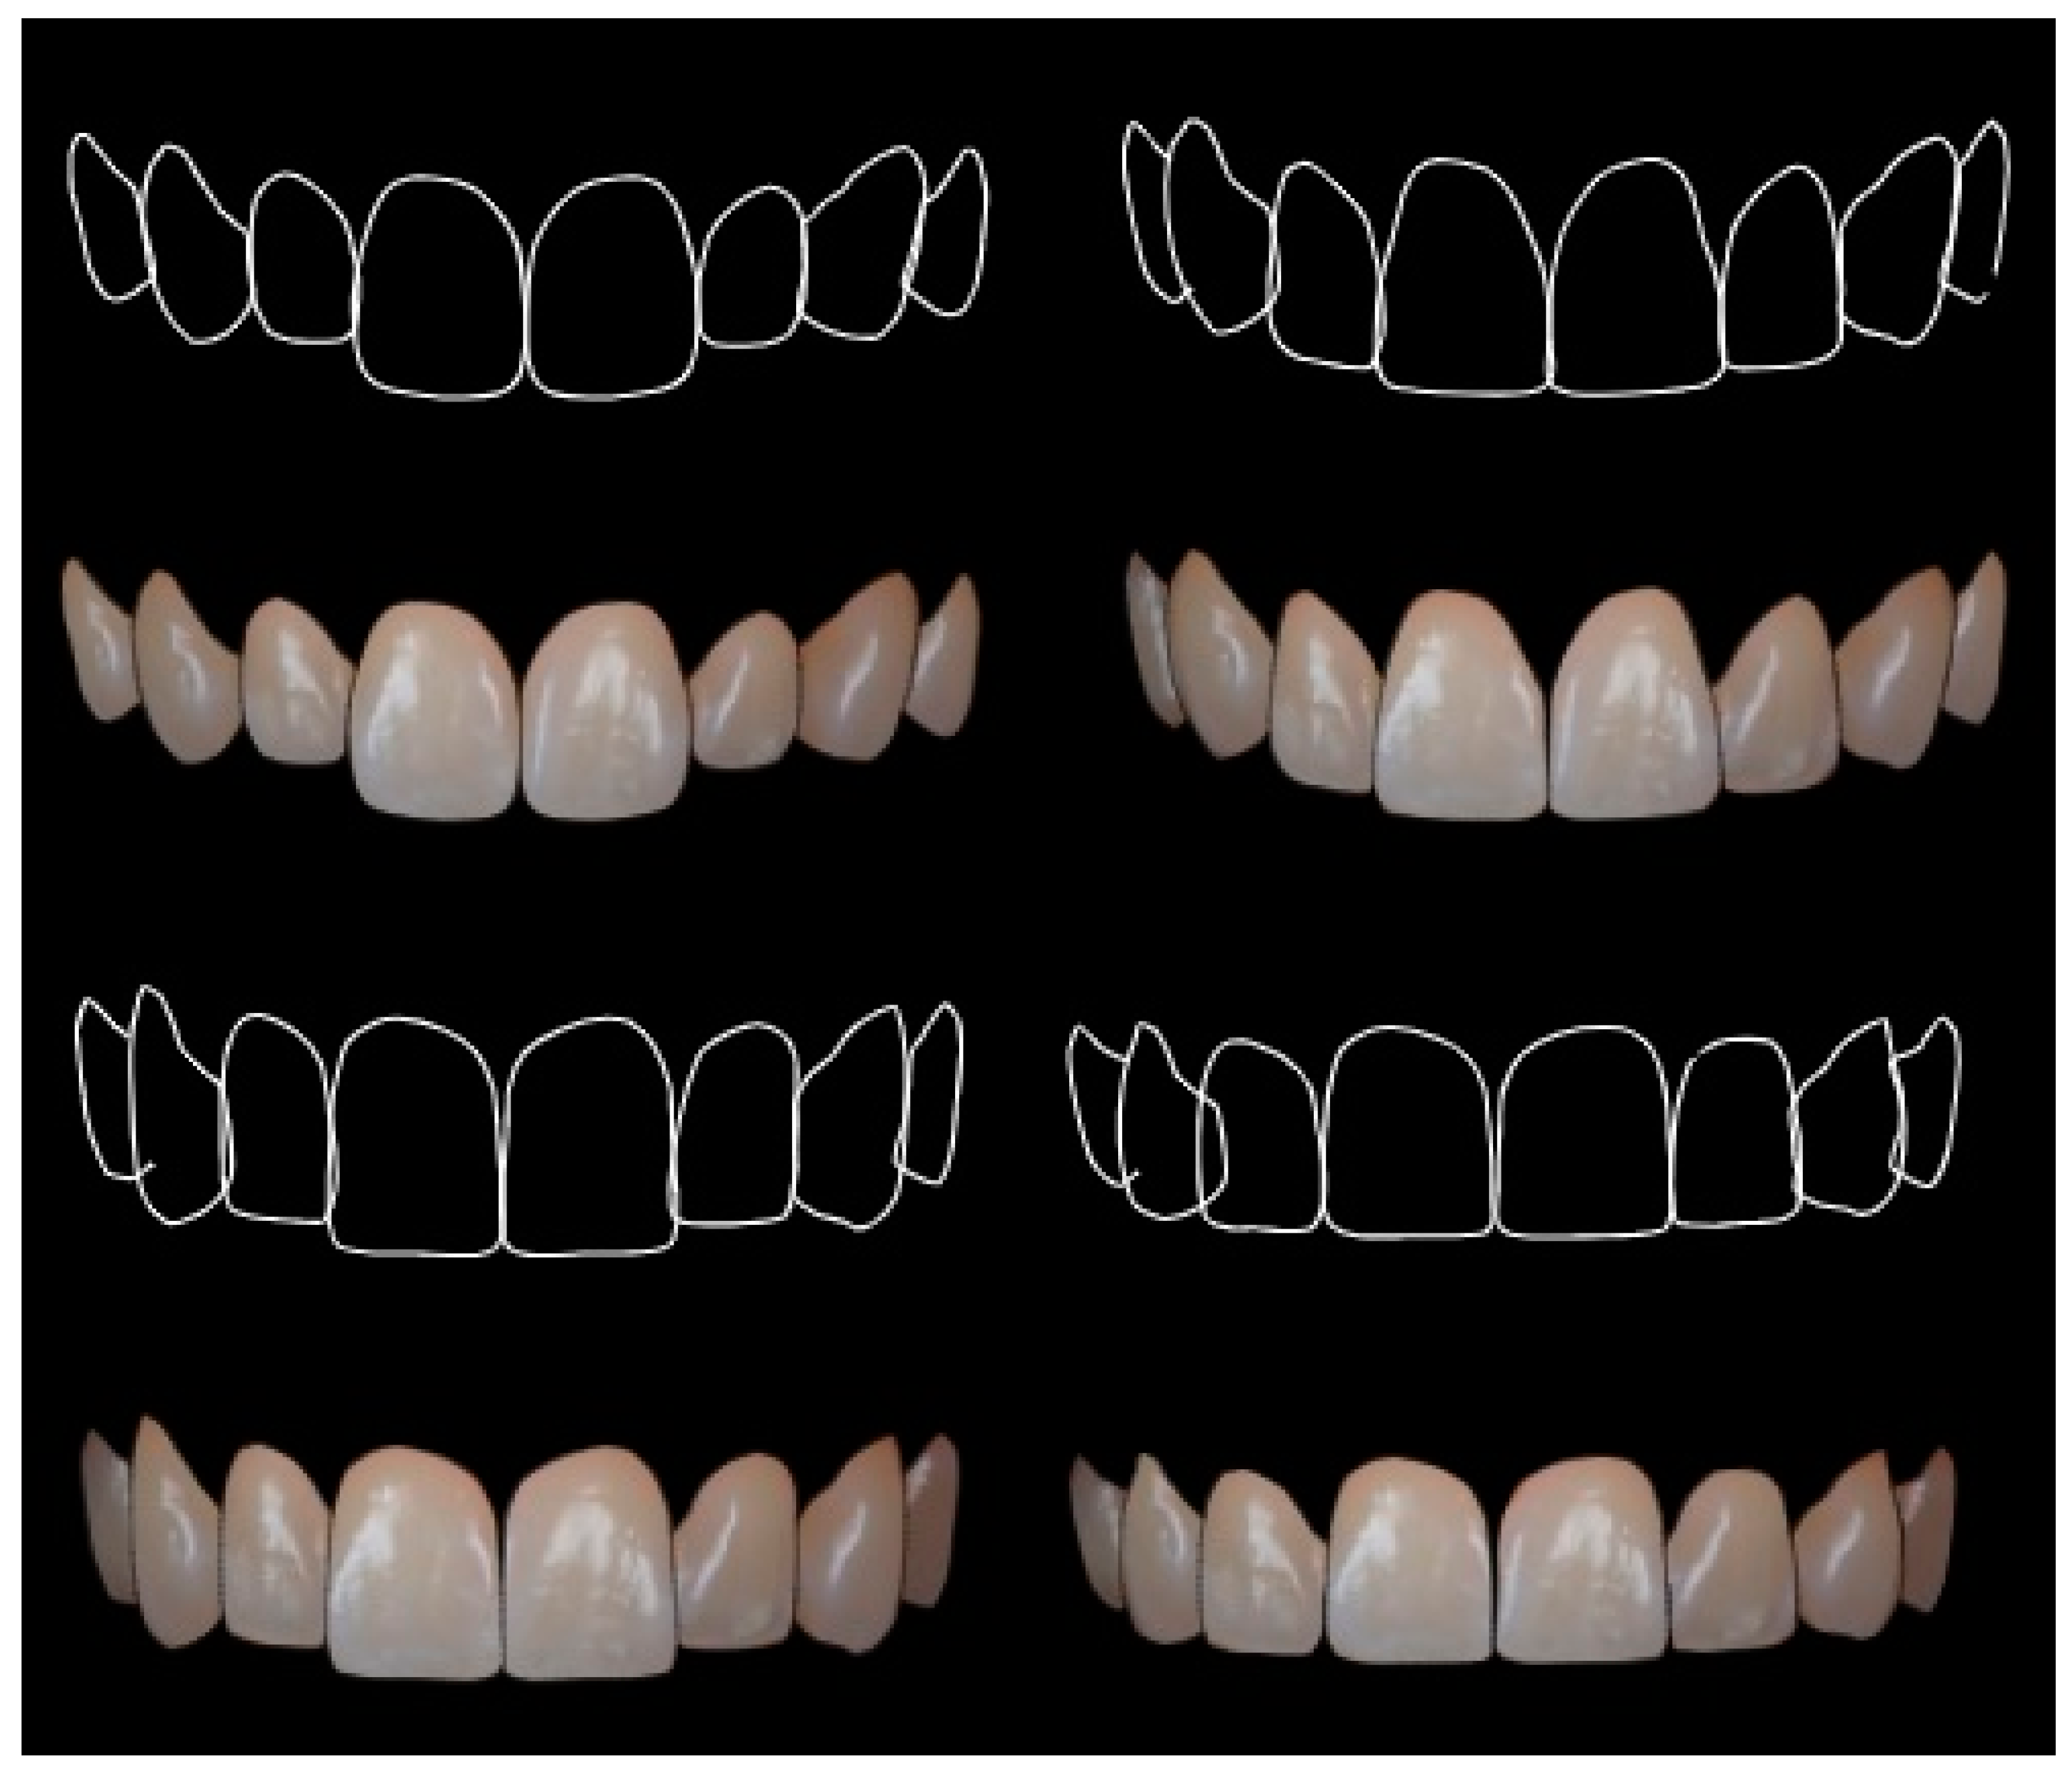

Digital Smile Design DSD Using Microsoft PowerPoint Full Protocol

DSD Digital Smile Design Online Presentation

Another Digital Smile Design Powerpoint Template you can download

- Implant CE Article Digital Smile Design In Implant Dentistry

- DSD Digital Smile Design Online Presentation